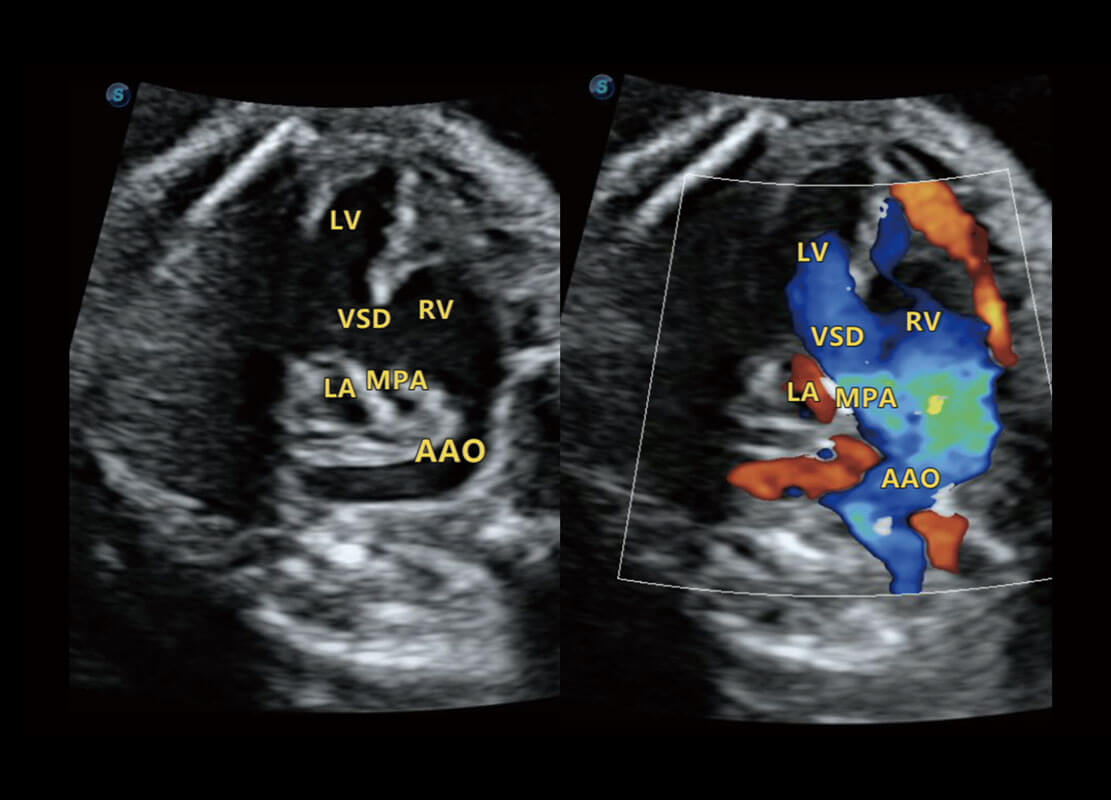

右室双出口

胎心容积成像